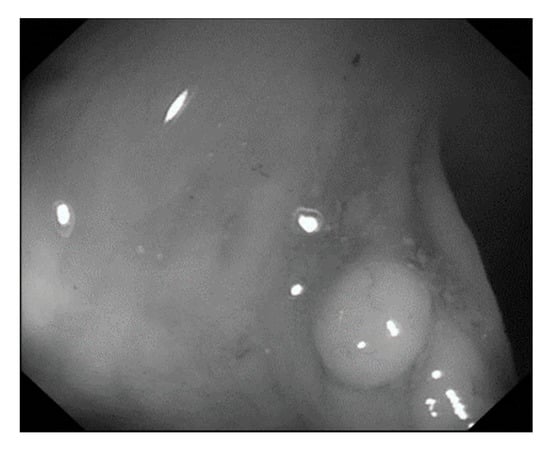

Figure 7.

Polyp image before gray scaling.

Figure 8.

Polyp image after gray scaling.